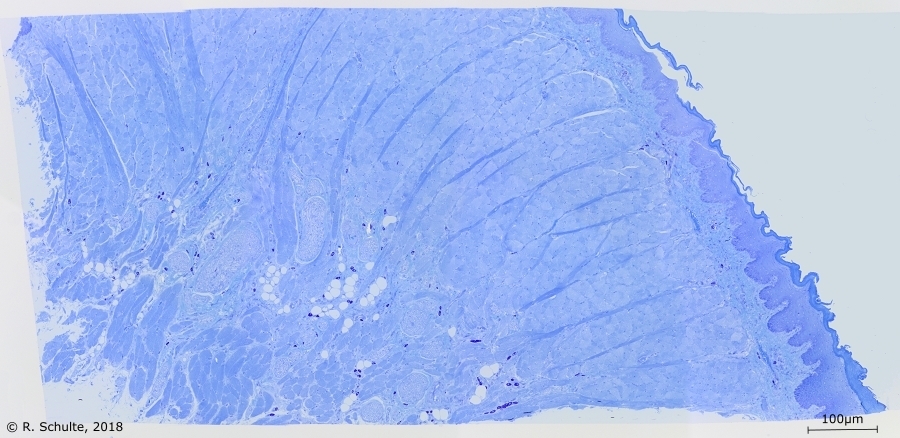

Gegranuleerde mestcellen in tong van een muis.

Mestcellen in een muizen tong preparaat

In de hier getoonde coupes van een muistong zijn geen mestcel ophopingen te zien maar wel zijn de mestcellen in grote hoeveelheden aanwezig. In bijvoorbeeld menselijk weefsel komen veel minder mestcellen voor[Red].

In ‘A practical guide to the histology of the mouse’ is te lezen dat bij knaagdieren deze grote hoeveelheid volledig normaal is en dus geen

ziektebeeld is. Citaat: “Heavily granulated mast cells are commonly seen in normal rodent tongues and can be demonstrated with toluidine blue staining.”[5]